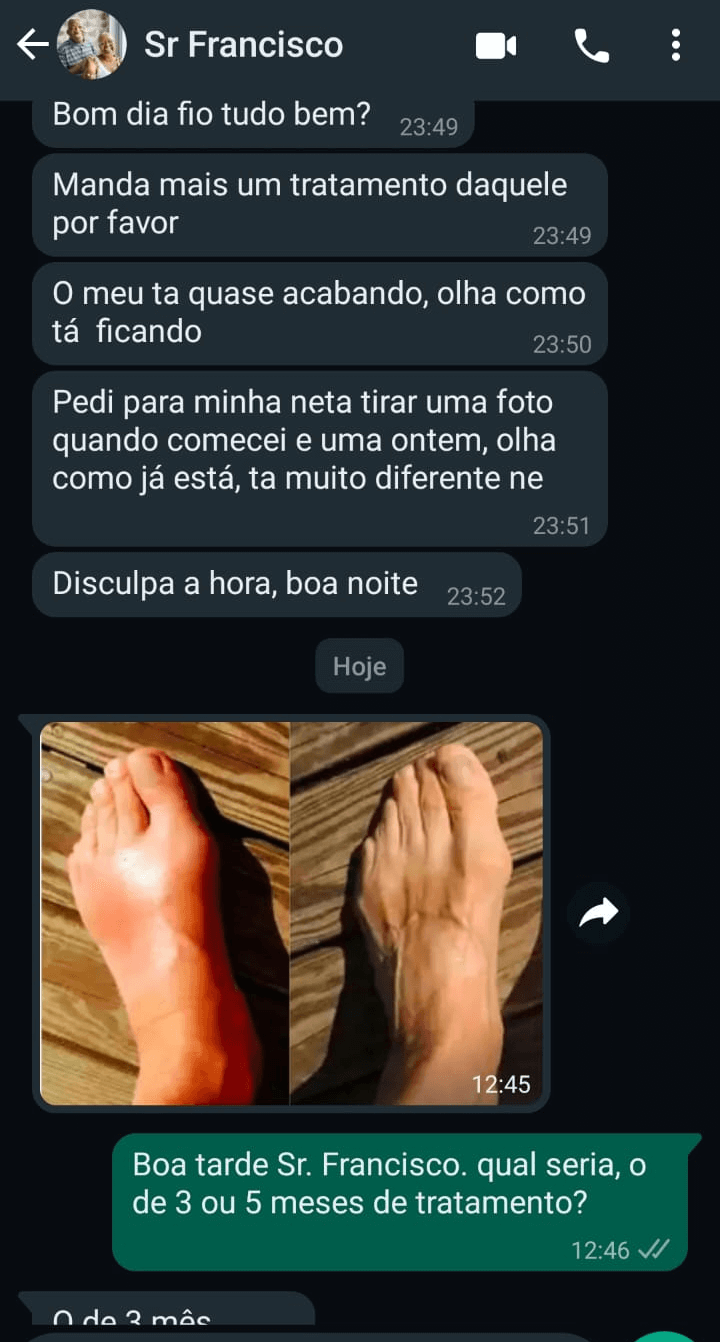

ARTRITE, ARTROSE E REUMATISMO

Sinta o alivio imediato nas dores intensas causadas pela artrite, artrose e reumatismo.

Zingiber Officinalle

Poderoso Anti-inflamatório natural usado na China e Ásia tropical há milhares de anos. Combate problemas ligados à dor, inclusive artrite reumatoide, artrose, bursite, dor lombar, dor na coluna, quadril e joelho inchado.

FAÇA PARTE DO NOSSO TIME DE CLIENTES QUE AMARAM

É recomendando o uso por 3 meses consecutivos para obter os melhores resultados. No entanto, há vários relato de pessoas que já sentem ótimos resultados já nos primeiros dias de uso.